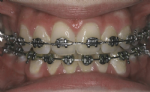

Die auf die Zähne geklebten Brackets sind in der Regel aus Stahl und daher silberfarbig. Stählerne Brackets sind besonders schlank und bieten eine sehr exakte Führung für die aktiven Elemente der Zahnspange. In manchen Fällen ist es auf Grund der beruflichen Situation des Patienten nötig, möglichst unauffällige, also zahnfarbene Brackets zu verwenden.

Auch die Verwendung goldfarbiger Brackets (und zum Teil auch Drähte) ist möglich und verbessert oft entscheidend die kosmetische Wirkung. Die Qualität derartiger goldfarbener Brackets ist dabei ähnlich gut wie die der silbernen.

Besonders elegant ist die Verwendung einer Kombination zahnfarbener und goldfarbiger Brackets.